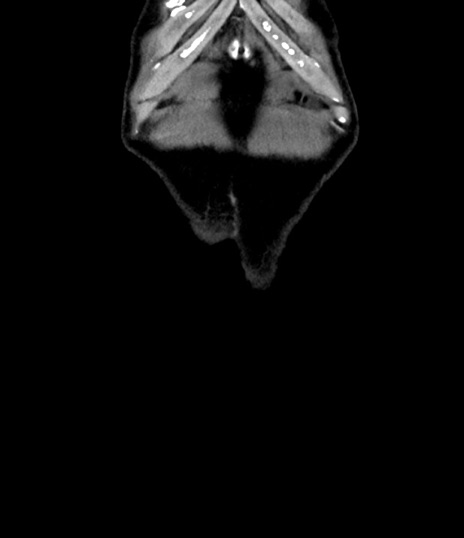

症例8(冠状断像)

【症例】 60歳代男性

【主訴】 黒色吐物

【現病歴】 4日前から嘔気自覚、2日前の朝食後にも嘔気あり、自分で手で嘔吐反射起こし嘔吐したところ血が混ざっていたため受診。

【既往歴】 5年前汎発性腹膜炎を伴う急性虫垂炎で手術、高血圧、前立腺肥大症、高脂血症

【身体所見】 腹部正中に手術癩痕あり 腹部平坦・軟圧痛なし膨満感あり

【データ】WBC 8400、CRP 4.54